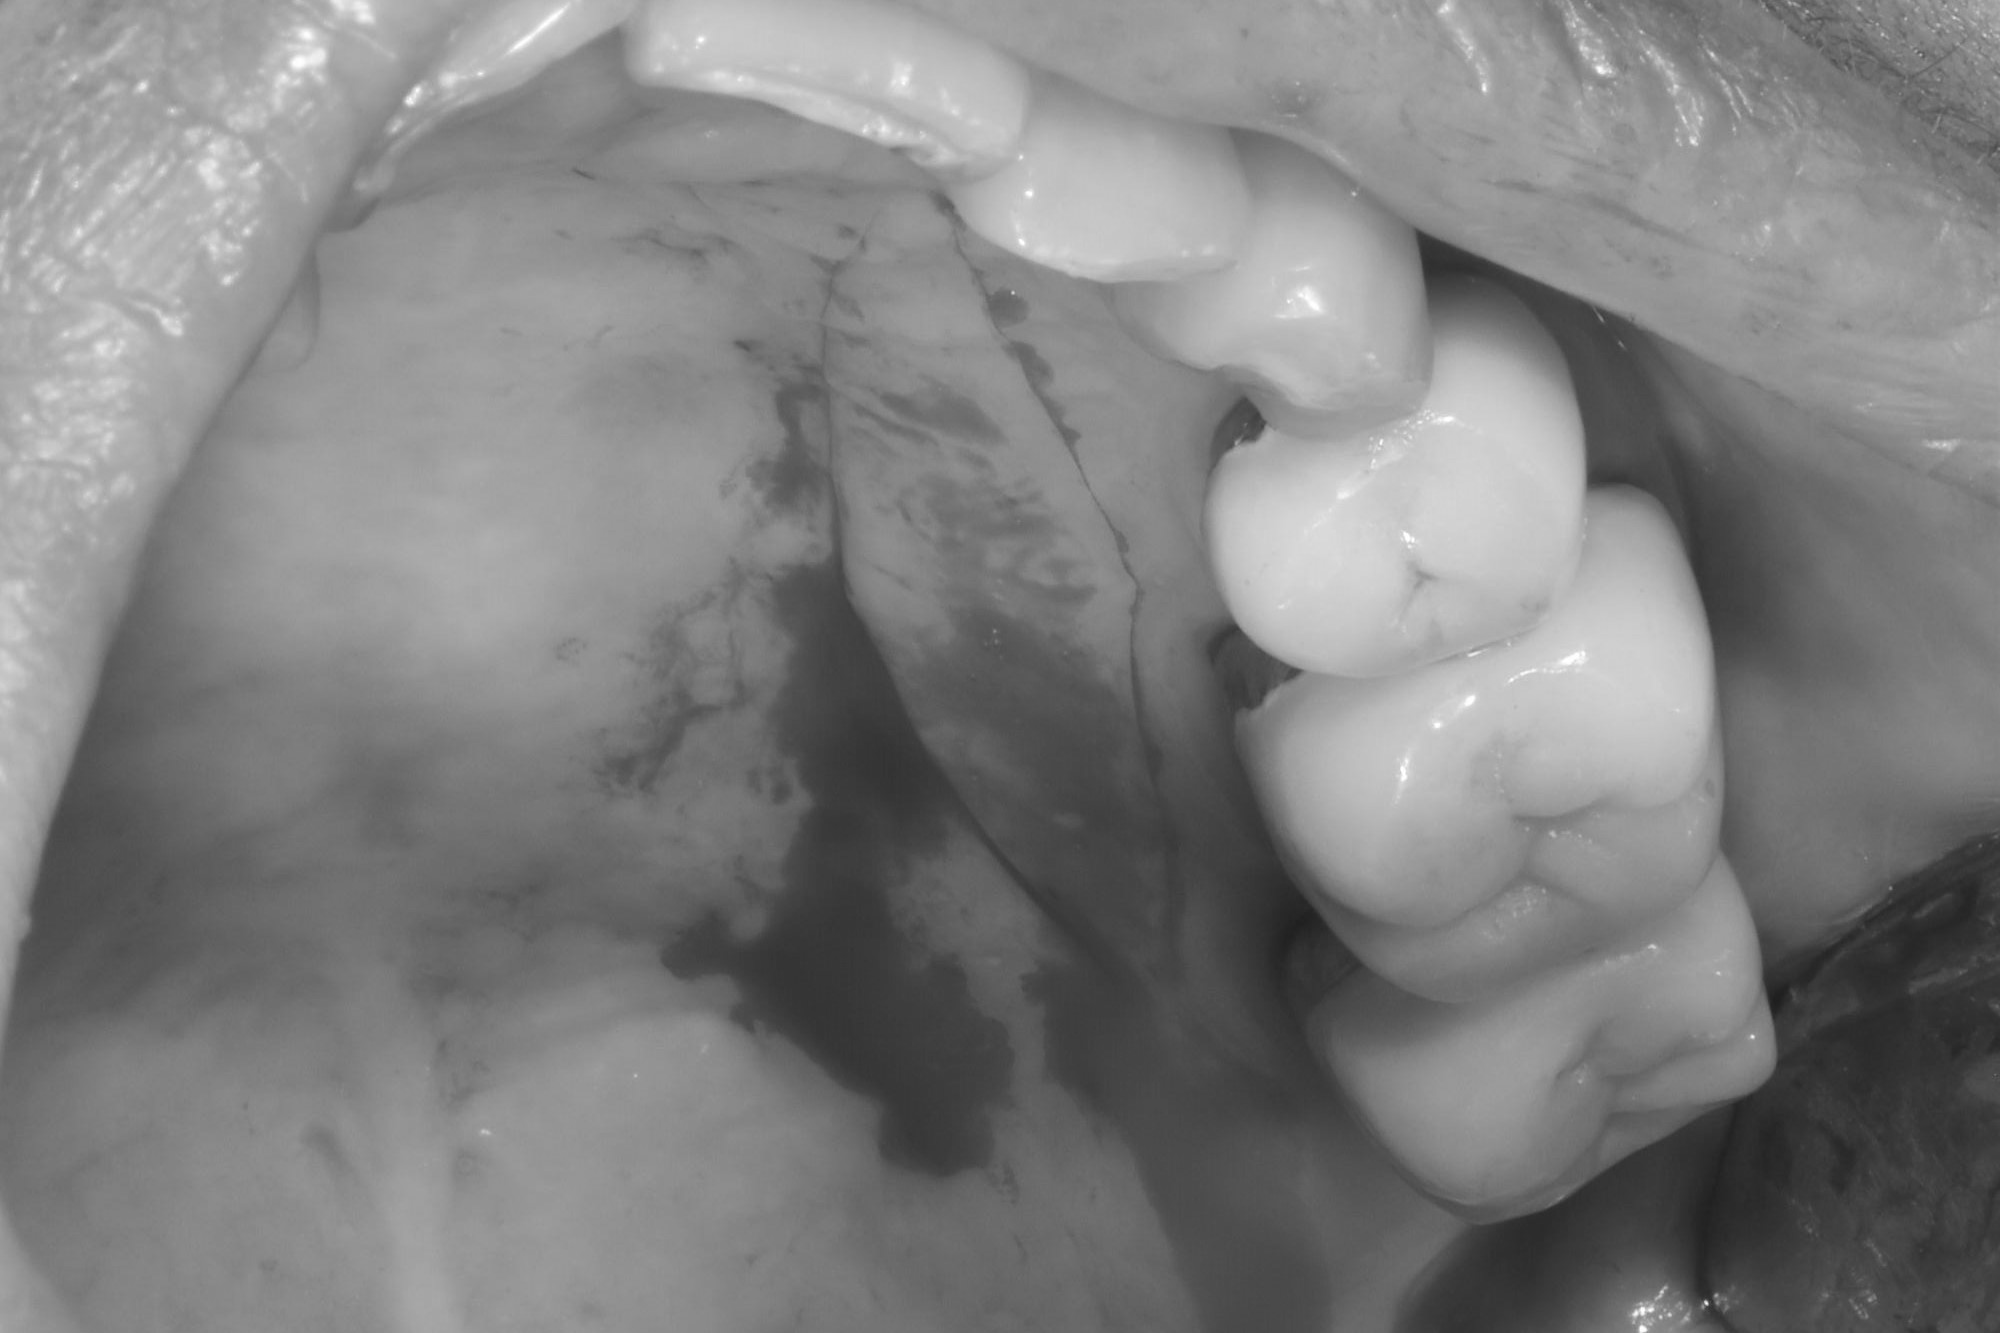

牙齦移植術(補肉)

手術案例

術前加術後案例

案例三